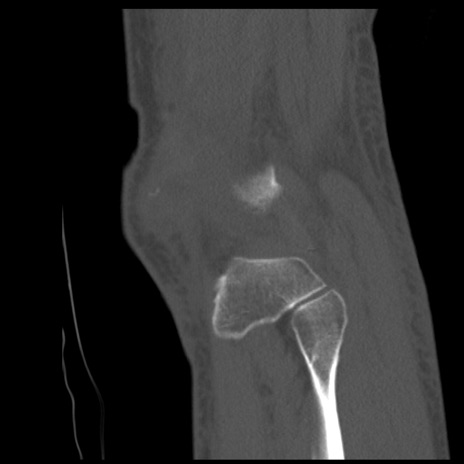

症例28 右膝関節CT(矢状断像)

右膝関節CT